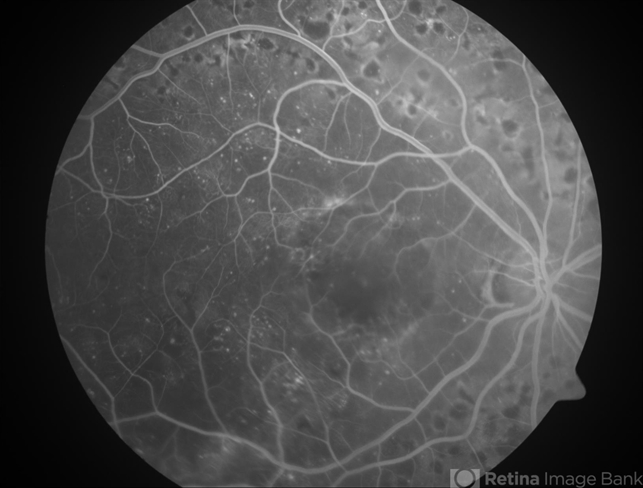

- diabetic retinopathy circinate, diabetic macular edema

- Diabetic macular edema - leaking microaneurysms.